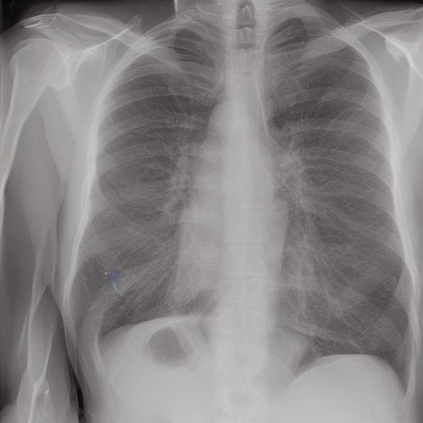

To address these issues, we propose a novel Adaptive patch-word Matching (AdaMatch) model to correlate chest X-ray (CXR) image regions with words in medical reports and apply it to CXR-report generation to provide explainability for the generation process. AdaMatch exploits the fine-grained relation between adaptive patches and words to provide explanations of specific image regions with corresponding words. To capture the abnormal regions of varying sizes and positions, we introduce the Adaptive Patch extraction (AdaPatch) module to acquire the adaptive patches for these regions adaptively. In order to provide explicit explainability for CXR-report generation task, we propose an AdaMatch-based bidirectional large language model for Cyclic CXR-report generation (AdaMatch-Cyclic). It employs the AdaMatch to obtain the keywords for CXR images and `keypatches' for medical reports as hints to guide CXR-report generation. Extensive experiments on two publicly available CXR datasets prove the effectiveness of our method and its superior performance to existing methods.